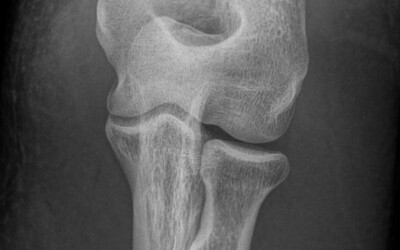

Wrist and hand osteoarthritis.

Created:15-07-2012 || Updated: 07-02-2020